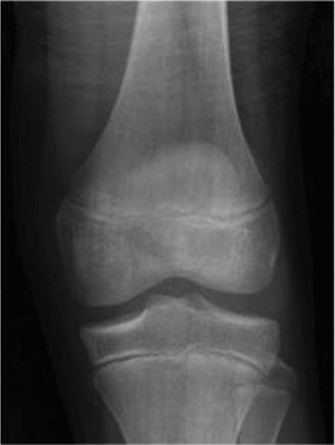

The patient then obtains the following radiograph (Fig. 10–22) which confirms the diagnosis of an OCD lesion of the medial femoral condyle. An MRI is then ordered to examine the lesion further. A T2 image is shown in Figure 10–23.

Figure 10–22

The correct answer is (D). The patient has several months of localized knee pain which is limiting his ability to engage in age-appropriate activities (i.e., sports). The physical examination maneuver described (Wilson’s test) is utilized to diagnose an osteochondritis dissecans (OCD) lesion of the knee. In a pediatric patient with localized pain which is limiting his/her activities, the next step in management should include a radiographic work-up prior to prescribing treatment (i.e., reassurance or physical therapy). Plain films should precede advanced imaging such as an MRI. The tunnel/notch view profiles the posterosuperior articular surface of the medial and lateral condyles where many OCD lesions of the knee are located which can be missed on a standard AP and lateral series of the knee.